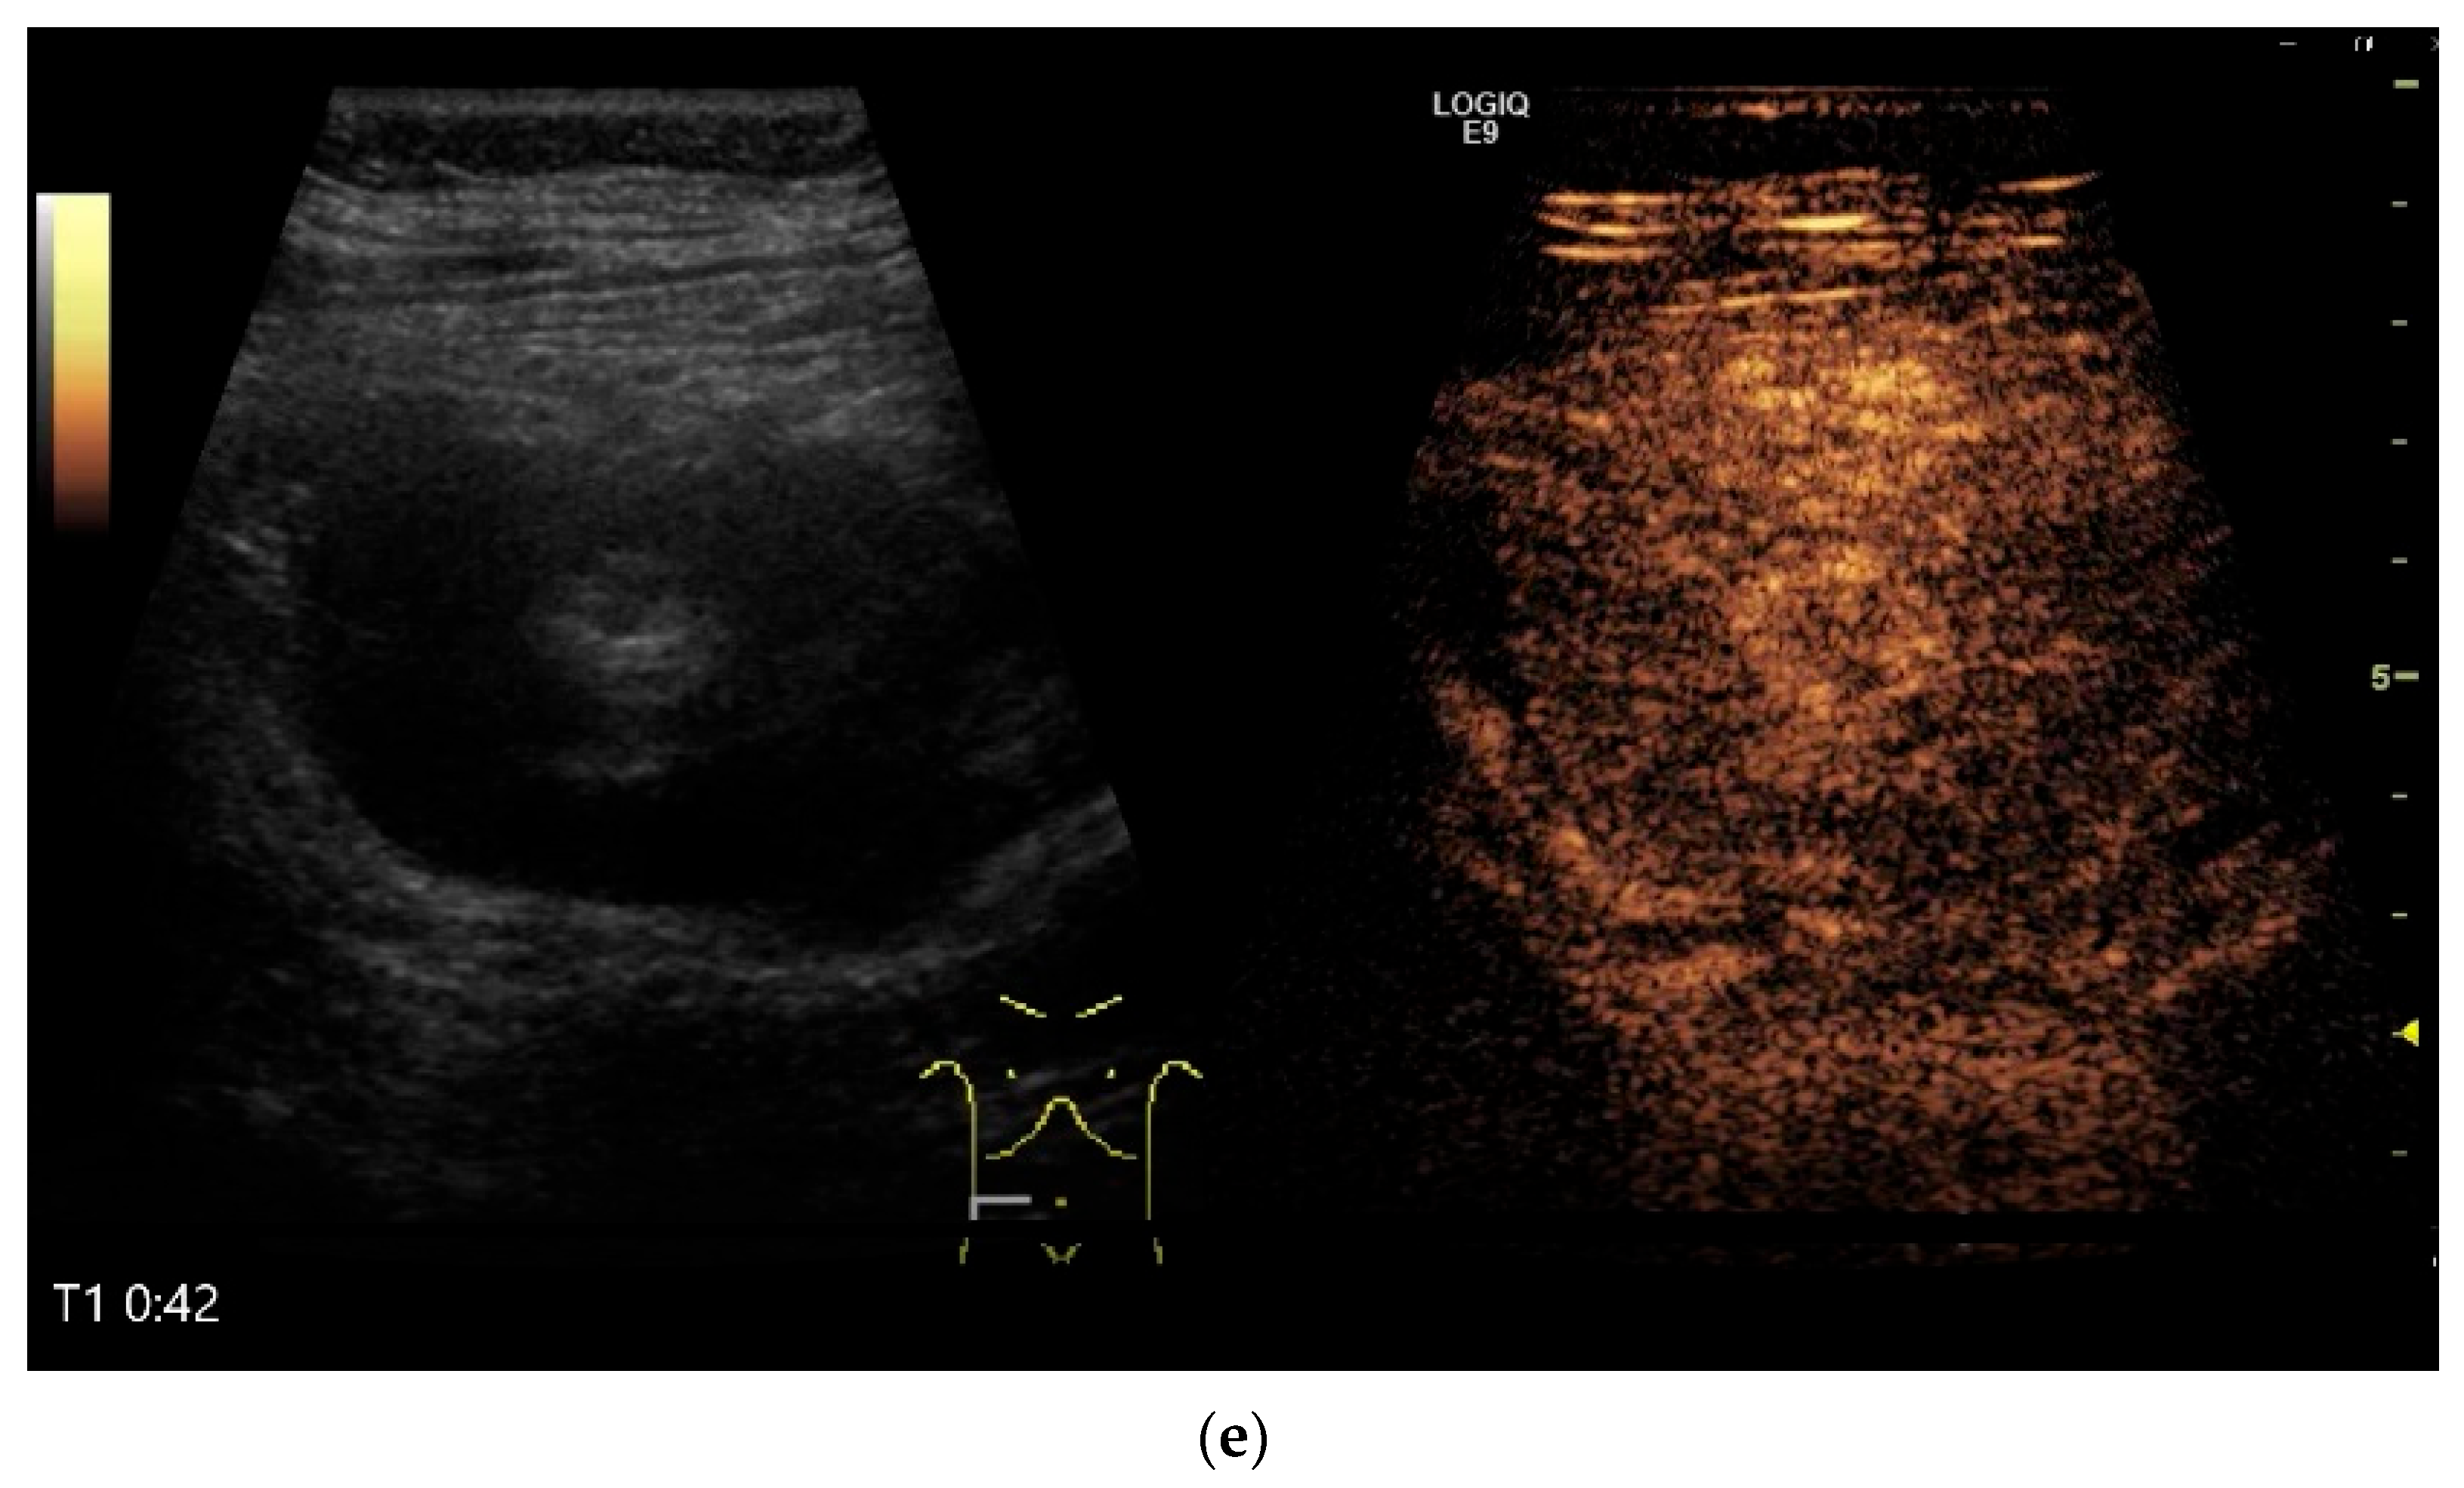

Figure 10.

Diffuse large B-cell lymphoma (DLBCL). In the right mid-lower abdomen, a large, smoothly circumscribed mass is present around the ileum (“pseudo kidney sign” (a)). Using a high-resolution linear transducer, the mass appears smoothly circumscribed and almost anechoic (b). The ileum runs centrally, and the echogenic wall is clearly defined (c). This wall does not merge into the mass. Since the mass is almost anechoic, it is also difficult in different transducer positions to distinguish whether it is a liquid lesion or a solid mass (b,c). CEUS with 2.4 mL SonoVue (9 MHz linear transducer) shows homogeneous arterial enhancement (d), but the intensity decreases with time in the venous phase (e). The ileal wall enhancement centrally within the mass is more intense than that of the tumor (d,e).